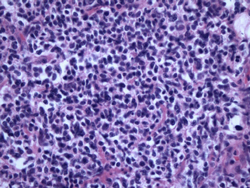

미만성거대 B세포 림프종의 조직검사 소견

2009.08.20